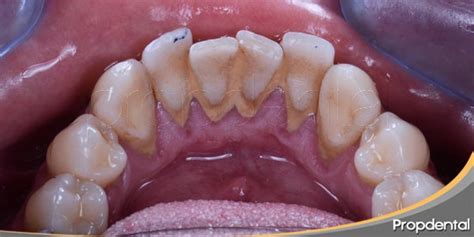

El sarro, también conocido como cálculo dental, es una placa endurecida que se forma en los dientes cuando la placa bacteriana no se elimina eficientemente. Está compuesto principalmente por minerales procedentes de la saliva y residuos alimenticios.

- Sarro supragingival: este sarro se forma en la superficie de los dientes, fuera de la encía.

- Sarro subgingival: este sarro se forma debajo de la línea de la encía.

El sarro puede ser de color amarillento, marrón o verdoso en casos más severos.